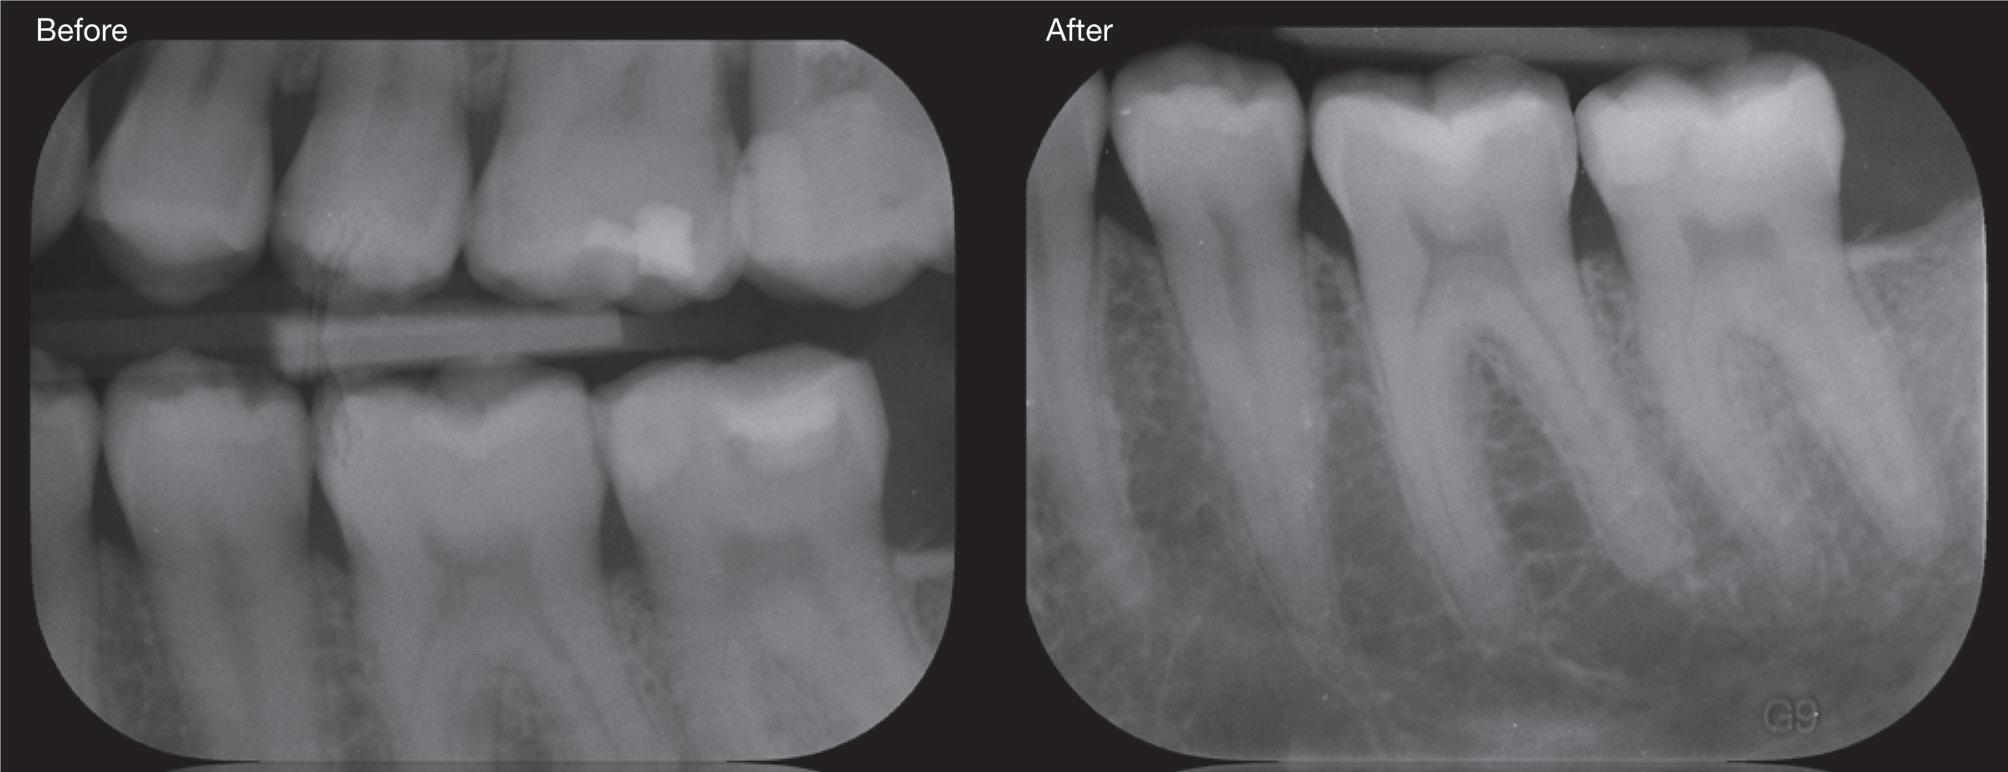

The standardisation of treatment procedures has resulted in less emphasis on craftmanship. I have quite a few gold restorations in my own mouth, two of which were placed there by a very fine dentist in 1968, both are still intact with no breakdown around the margins and both the teeth are functioning well, despite one of them having been root treated with silver points at the time. I take regular radiographs and there are absolutely no problems. I placed a number of gold restorations in my wife’s mouth before we were married in 1973 and they, too, are all still functioning well. And yet my laboratory, which

employs more than 30 technicians, has only one person who is still capable of producing good metal margins and despite all the emphasis on digital restorations and aesthetics, the dentists that I treat as patients prefer gold in their own mouths and for their families wherever possible.

When I was working and studying in the U.K. in the very early 70s, I became interested and then became involved in implant dentistry. I was lucky to have mentors like Hans Orlay, Ron Cullen, Lou Caplan and others. One of my most vivid memories is of Leonard Linkow opening the First World Implant Congress in Paris in October 1972 with the words: “Behold the turtle, he only makes progress when he sticks his neck out”.

We already knew at that time that Titanium was biocompatible and that cells could grow towards it without needing an intermediary and this resulted in osseointegration. One of the practices where I worked was across the road from the Hawker Sidley aircraft factory which gave me access to pure Titanium. I obtained some pure Titanium, cylindrical wire which I planned to use if I ever decided to try doing some endodontic stabilisers as I figured that this would be better than the CoCr wire that Hans Orlay was using at the time.

I brought this back to Melbourne with me, together with my rather primitive implant kit, as well as a Kurer Post kit - no TGA rules in those days.

dry heat furnace, cut it to length less some 5 mm, coated it in endodontic sealer 10 mm short of the end to make sure that I didn’t extrude sealer past the apex, tapped it into place using my implant hammer and a Unitek pin placement tool and then using G.P. points, I sealed the tapering part of the root canal. I placed an amalgam seal on the lingual. The tooth became discoloured, the patient got married and moved to Queensland. I lost contact with him in the late 70s.

Fifteen years ago, I had to refer an elderly patient to an Oral Surgeon to have some teeth removed. We got a phone call at the surgery from her daughter who wanted to understand what was happening. I called back what was a Queensland number and identified myself to the man who answered the phone. On hearing my name, he identified himself and asked whether I remembered him. Of course I did. I asked him whatever happened to that tooth. He said that it didn’t cause any problems but that it had turned jet black and he and his wife got sick of looking at it. He’d had it extracted some 5 years earlier and it was replaced by a conventional implant. I asked him about the teeth either side of it and he said that they were still there and perfectly OK.

In 1975, one of my patients who was 18 years old became involved in a car accident; he hit the steering wheel with his chin and sustained 2 horizontal fractures in his 31, both quite a way subgingivally. The 41 and 32 were intact. The normal treatment at that time would have required extraction of the 31 and the placement of a partial denture or a bridge to replace the missing tooth.

Knowing that he had nothing to lose, he agreed to let me experiment on him. I extirpated the 31, drilled 10mm past the apex using a sterile Kurer Post spiral drill that matched the diameter of my titanium wire. I sterilised the Titanium using a

Yes, I did stick my neck out, but the result ended being a lot better for the patient than if we had opted for a bridge or a partial denture. The biological cost was negligible and we bought him 30 years of function until a better and more modern treatment became available.

In the current regulatory environment, treatment such as I described is not only illegal and would result in crippling fines being imposed by the TGA, but possibly result in losing one’s right to practice. If I had made a conventional bridge, the teeth either side would have been compromised and possibly lost by now, a partial denture would have caused periodontal problems.

One case does not prove anything, but the result speaks for itself and sadly the option to use our knowledge and initiative is no longer open to us.